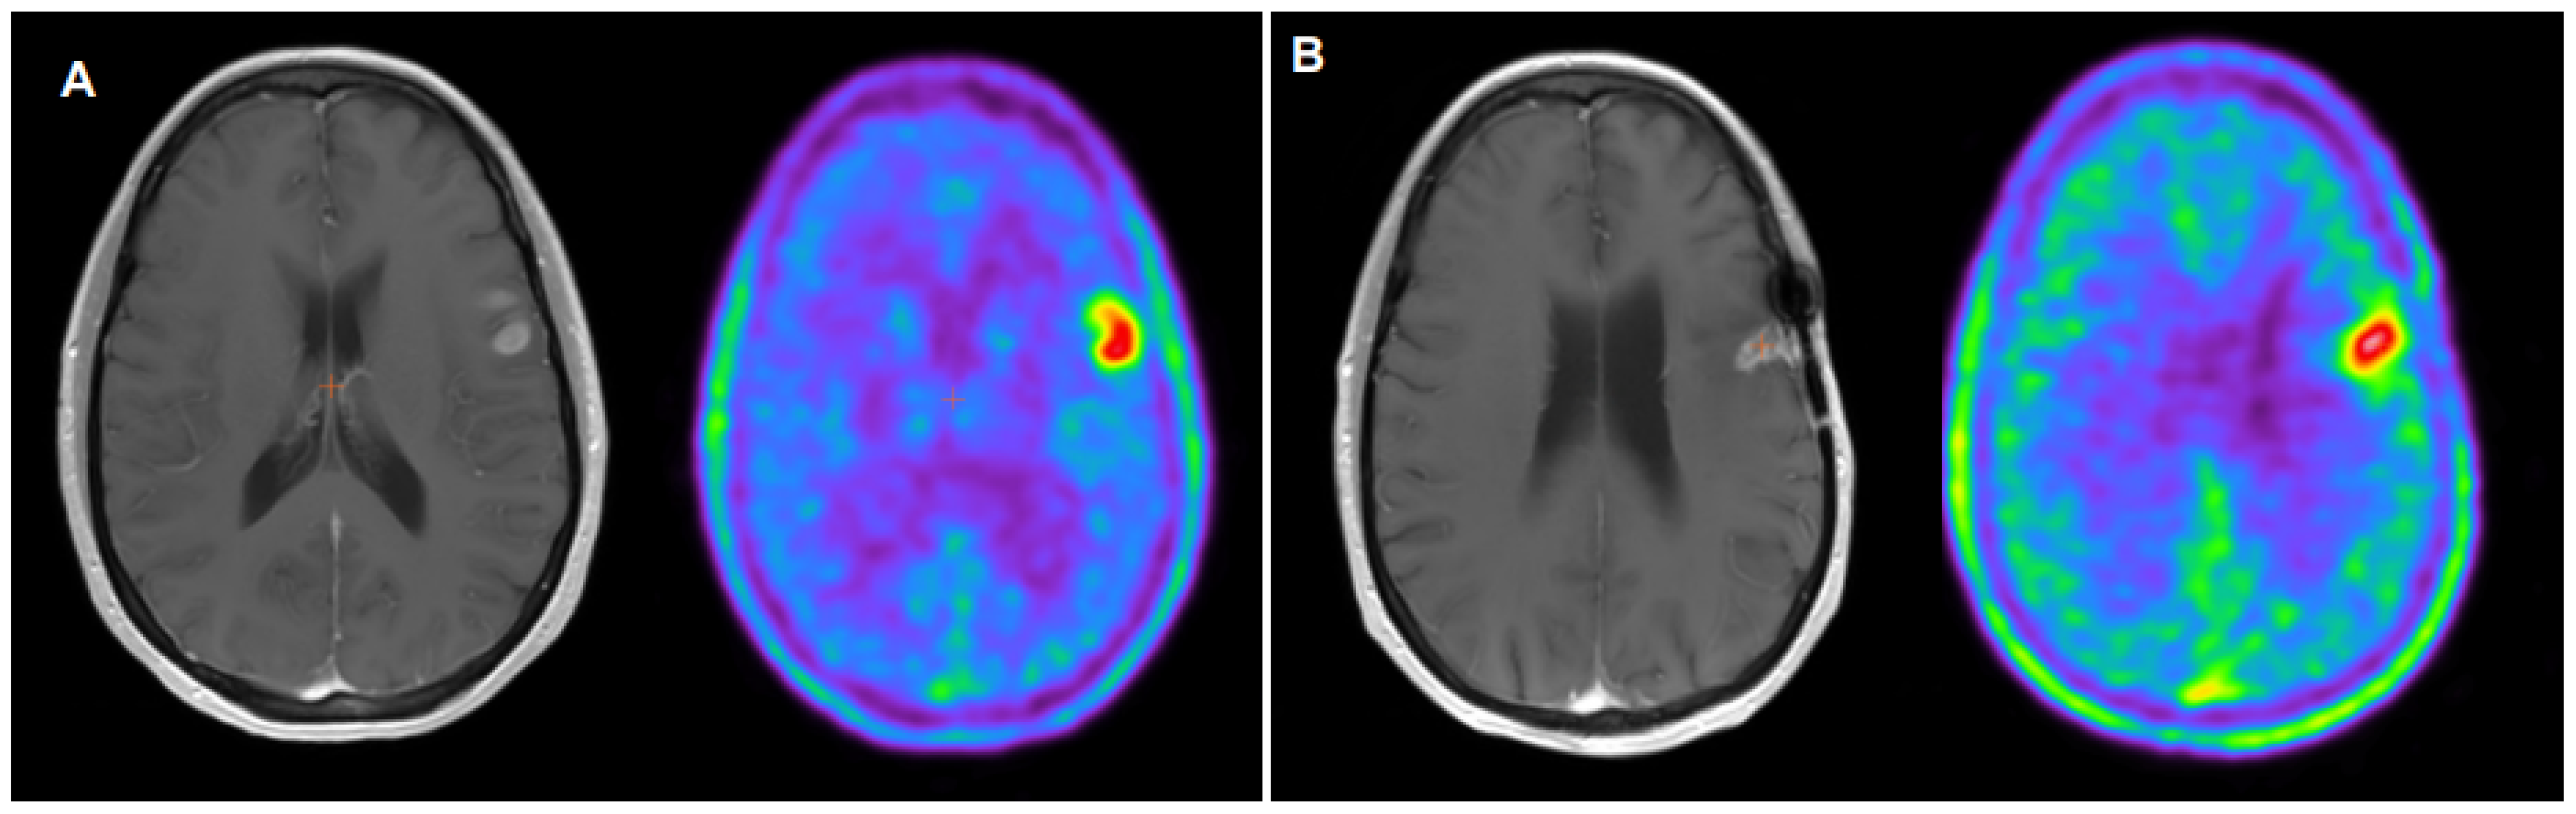

- Galldiks, N.; Dunkl, V.; Stoffels, G.; Hutterer, M.; Rapp, M.; Sabel, M.; Reifenberger, G.; Kebir, S.; Dorn, F.; Blau, T.; et al. Diagnosis of pseudoprogression in patients with glioblastoma using O-(2-[18F]fluoroethyl)-L-tyrosine PET. Eur. J. Nucl. Med. Mol. Imaging 2015, 42, 685–695. [Google Scholar] [CrossRef] [PubMed]

- Kebir, S.; Fimmers, R.; Galldicks, N.; Schäfer, N.; Mack, F.; Schaub, C.; Stuplich, M.; Niessen, M.; Tzaridis, T.; Simon, M.; et al. Late Pseudoprogression in Glioblastoma: Diagnostic Value of Dynamic O-(2-[18F]fluoroethyl)-L-Tyrosine PET. Clin. Cancer Res. 2016, 22, 2190–2196. [Google Scholar] [CrossRef] [PubMed]

- Werner, J.M.; Stoffels, G.; Lichtenstein, T.; Borggrefe, J.; Lohmann, P.; Ceccon, G.; Shah, N.J.; Fink, G.R.; Langen, K.J.; Kabbasch, C.; et al. Differentiation of treatment-related changes from tumor progression: A direct comparison between dynamic FET PET and ADC values obtained from DWI MRI. Eur. J. Nucl. Med. Mol. Imaging 2019, 46, 1889–1901. [Google Scholar] [CrossRef] [PubMed]

- Maurer, G.D.; Brucker, D.P.; Stoffels, G.; Filipski, K.; Filss, C.P.; Mottaghy, F.M.; Galldiks, N.; Steinbach, J.P.; Hattingen, E.; Langen, K.J. 18F-FET PET Imaging in Differentiating Glioma Progression from Treatment-Related Changes: A Single-Center Experience. J. Nucl. Med. 2020, 61, 505–511. [Google Scholar] [CrossRef] [PubMed]